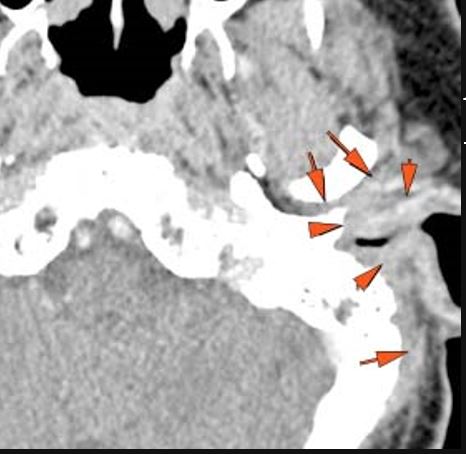

There is an erosive process, subperiosteal or otherwise spreading along the anterior-inferior aspect (extracranial aspect) of the petrous apex involving the bony Eustachian tube and/or carotid canal. [Yes/No]

There is bone erosion along the outer margin of the mastoid portion of the temporal bone. [Yes/No]

The sigmoid plate of the mastoid is eroded. [Yes/No]

There are dural reactive changes or a subperiosteal/epidural abscess along the sigmoid plate of the mastoid displacing the adjacent sigmoid sinus. [Yes/No]